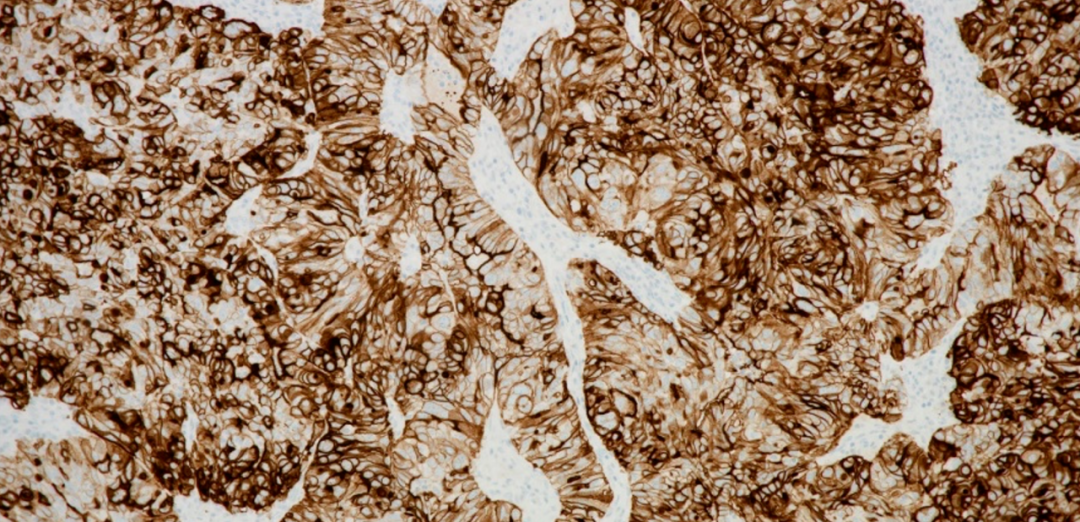

精准医疗、诊断先行。精准的伴随诊断是实现肿瘤患者个体化精准诊疗的先决条件,堪称靶向治疗最理想的“助攻”。此次获批的罗氏诊断VENTANA FOLR1抗体检测试剂,可通过染色强度水平为2+和3+的膜染色的肿瘤细胞百分比(% TC)确定FOLR1表达,辅助临床医生精确识别出适合接受索米妥昔单抗治疗的上皮性卵巢癌、输卵管癌或原发性腹膜癌患者。该检测可在罗氏诊断BenchMark 全自动免疫组化染色系统上实现全自动化运行,其经过规范化、标准化的临床验证,具有稳定性高、易判读等优势,可直接指导临床用药。